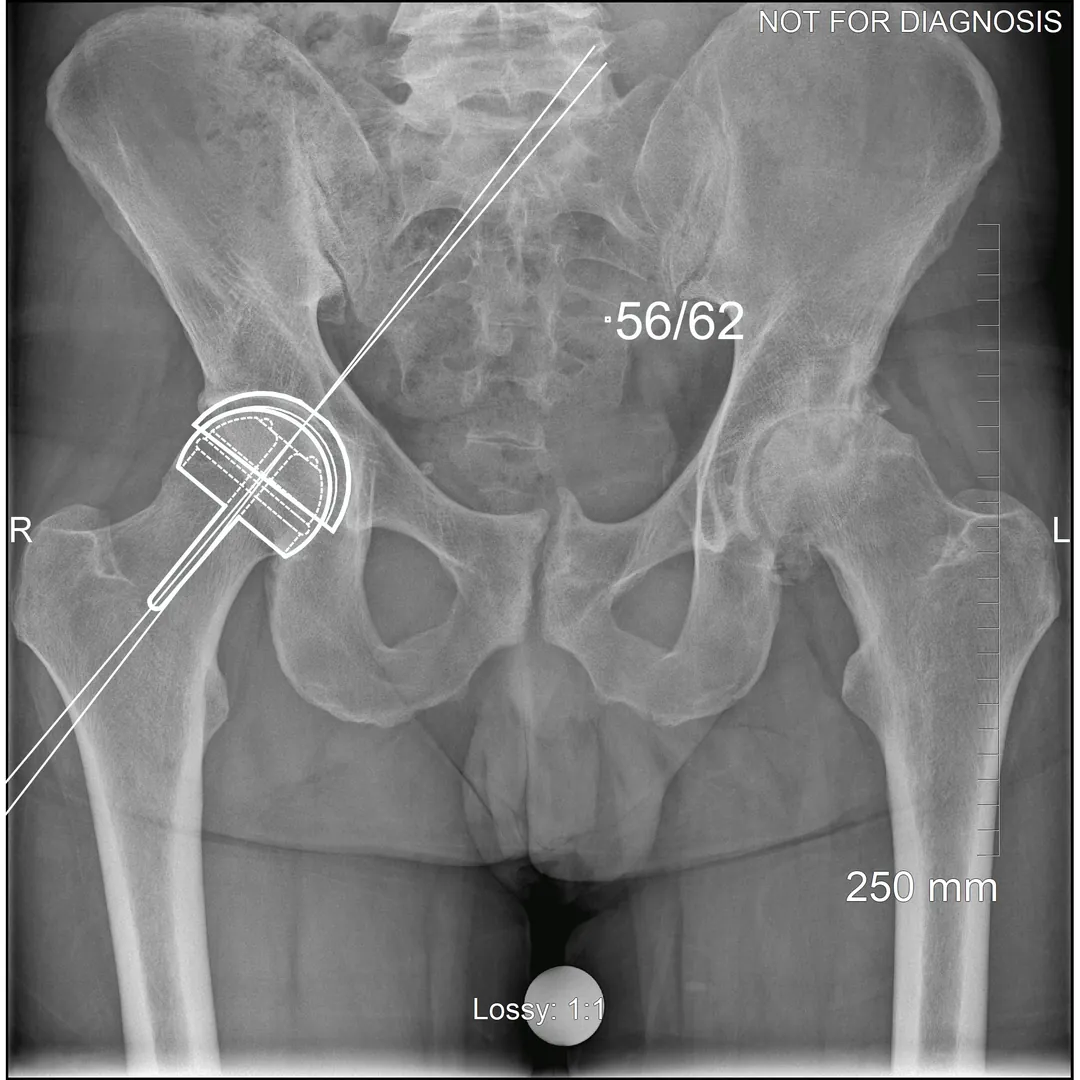

Hip resurfacing is a type of hip surgery used to treat hip arthritis, most commonly in younger and more active patients. Unlike a total hip replacement, hip resurfacing preserves more of your natural thigh bone. Instead of removing the entire femoral head (ball at the top of the thigh bone), the damaged surface is trimmed and covered with a smooth metal cap. The hip’s socket on the pelvis is also fitted with a metal cup.

- Have good bone quality and strong femoral neck bone

- Have a larger femoral head size

- Have a small femoral head size

Dr Grammatopoulos will review your X-rays and other imaging carefully to determine whether hip resurfacing is an appropriate option for you.

- Am I a candidate for hip resurfacing based on my X-rays and bone quality?

- What implant type and bearing surface would be used, and why?